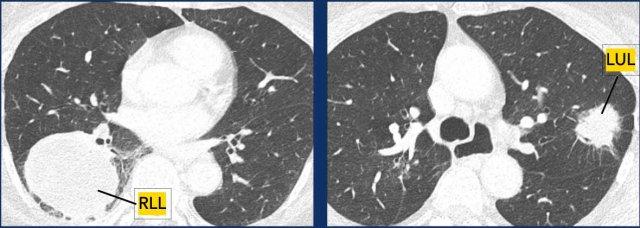

- Mỗi khối u được phân giai đoạn riêng biệt với phân loại TNM của chính nó. Ví dụ:

Ví dụ

- T4N0M0 ở thùy dưới phổi phải (RLL).

- T2bN1M0 ở thùy trên phổi trái (LUL).